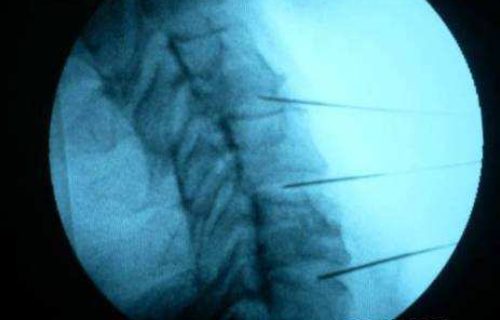

Bloqueos facetarios córtico anestésicos y con ozonoterapia

En nuestro medio en aquellos casos rebeldes a tratamiento, con persistencia del dolor a la movilización y restricción del movimiento sobre todo rotatorio, que no mejoran con el tratamiento conservador,…